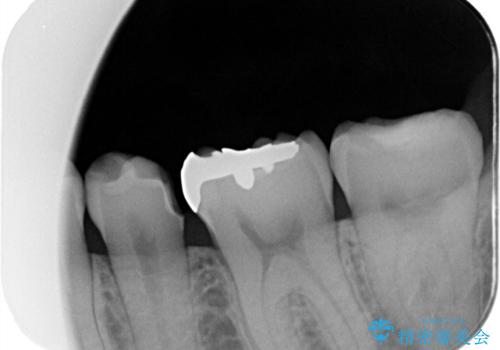

- 主訴:銀の詰め物が取れた、奥の銀の詰め物も一緒に白くしたい

保険適用のメタルインレーの脱離で来院されました。審美性、適合性、清掃性の観点から2本ともセラミックインレーでのやり替えとなりました。

保険適用のメタルインレーはセラミックやゴールドに比べるとプラークなどの汚れが付きやすく、また今回はそこまで大きなう蝕は広がっていませんでしたが、適合性に限界があるためインレーと歯質との境目で二次う蝕が発生する可能性が高くなります。